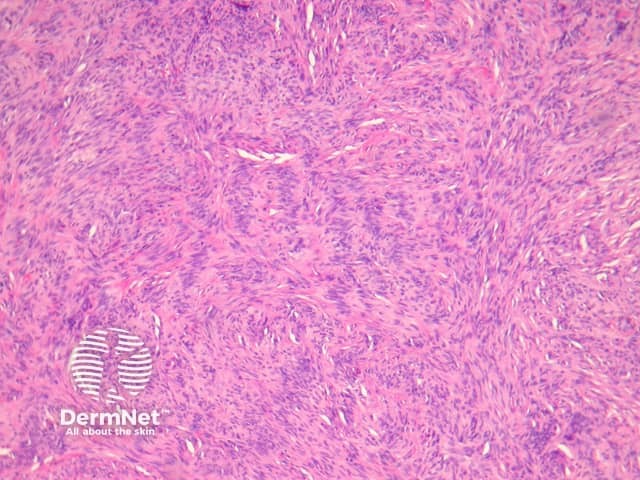

Fibrocollagenous dermatofibroma has a prominent storiform or swirled pattern, with a predominance of collagen and fibroblast-like cells (figures 13, 14). This subtype seems to be more common in rare cases of disseminated dermatofibroma seen in immunosuppressed patients.

Figure 13

Figure 14